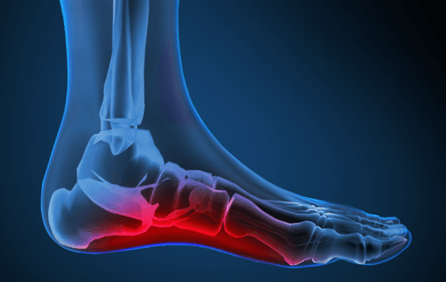

Increasing Circulation in the Lower Limb

The action of foot impulse technology (FIT) in reducing the risk of deep vein thrombosis (DVT) is well established. We hypothesized that intraoperative use of F......